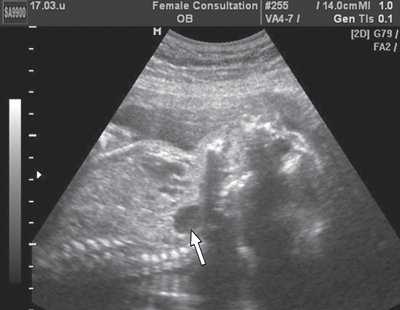

При сравнении изображения в 2D режиме, по которому производились первоначальные измерения, и ультразвукового среза, полученного ретроспективно из сохраненного объема видны ошибки, допущенные при измерениях (рис. 4), и прежде всего отсутствие четкой картины четырехкамерного среза сердца и небольшое увеличение снимка. На этом этапе работы использование новых технологий позволило нам более объективно оценить ранее полученные данные.

а) Нарушены правила оценки: нет четкого изображения четырехкамерного среза сердца.